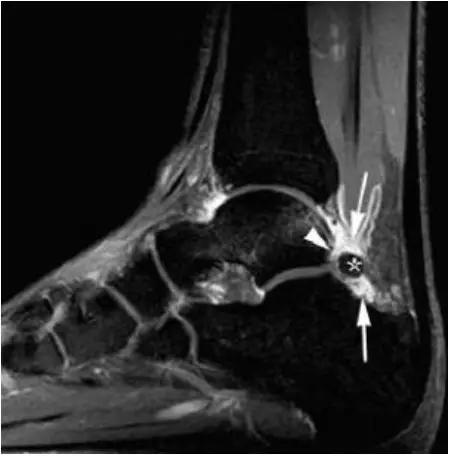

- 影像学表现为距骨后三角骨的存在或损伤以及距骨后突骨赘形成,导致踝关节跖屈受限,可伴随拇长屈肌肌腱鞘炎症及邻近滑膜不同程度的炎性增生 。

- MRI 检查示距后三角骨及周围软组织有水肿信号,距后三角骨和距骨之间正常的低信号纤维连接中断,出现液性信号。

3、MR表现:

- 三角籽骨或距骨后三角结构模糊和变形,T1WI信号降低, T2WI信号升高,

- 周围脂肪水肿,

- 踇趾长屈肌腱信号升高,见鞘膜积液,

- 胫骨后下跟骨上缘骨结构形态变化和信号异常,

- 三角籽骨和距骨退行性囊变。